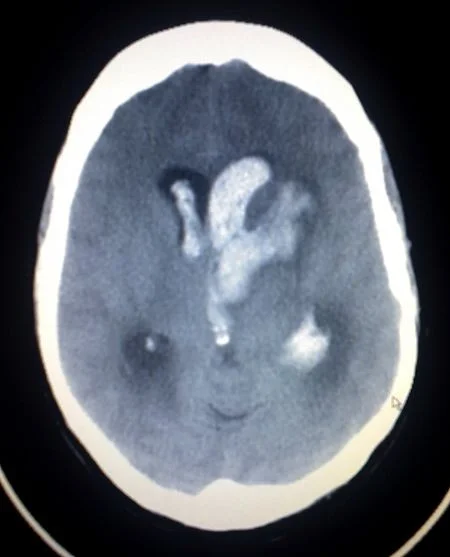

Subarachnoid Hemorrhage: SAH

Is bleeding into the subarachnoid space the area between the arachnoid membrane and the pia mater surrounding the brain. Traumatic SAH: Blow to lateral neck with resulting damage to Vertebral Artery. Signs and symptoms:

- Thunderclap headache.

- Oculomotor nerve abnormalities.

- Neck stiffness.

- Increase in blood pressure.

- Cardiac arrhythmias

Intracerebral Hemorrhage

Is when blood suddenly bursts into brain tissue, causing damage to the brain.